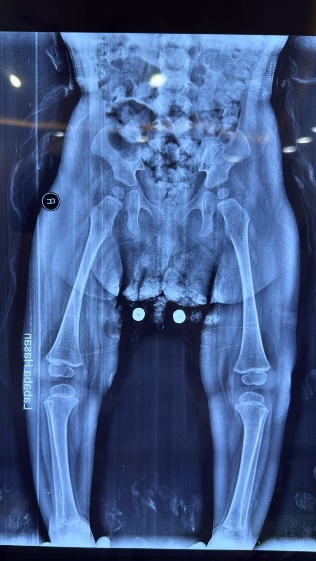

Skeletal: Short broad hands/feet, clenched fists, bilateral clubfoot.

Our patient’s manifestations—severe hypotonia, seizures, craniofacial dysmorphism, cortical blindness, and skeletal deformities—are consistent with previously reported PIGV-related cases [4,6,10]. Congenital heart disease (ASD) has occasionally been described in this subtype [7,11].

Figure 11: Skeletal deformities of the upper and lower limbs

Photographs showing short, broad hands with clenched fingers (upper image) and bilateral clubfoot deformities (lower image), consistent with skeletal abnormalities described in HPMRS.